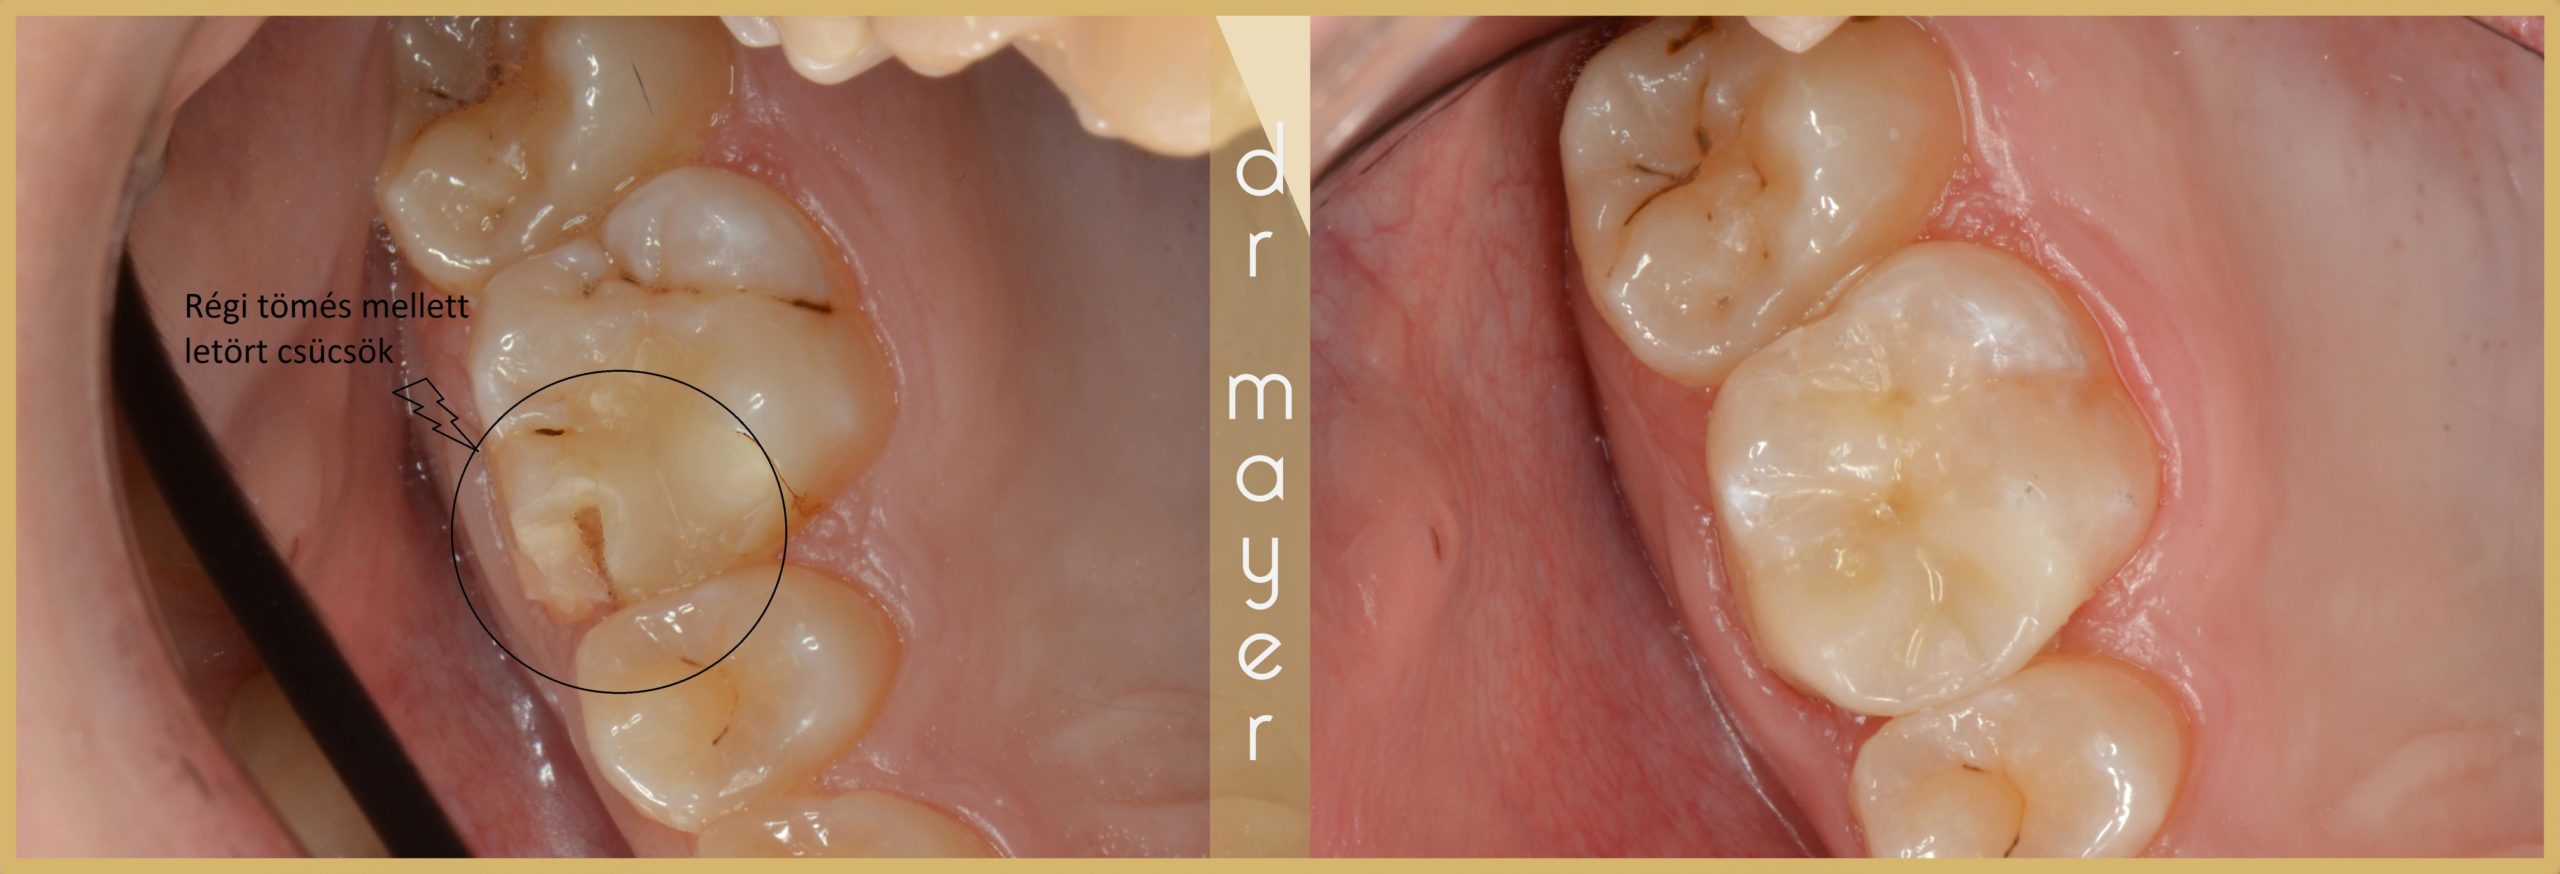

A következő eset egy szerencsésen letört fogat mutat be, amit Gradia betéttel láttunk el:

A kép bal oldalán egy teljesen letört csücskű felső első nagyörlő látható. A kép jobb oldalán pedig ugyanaz a fog betéttel helyreállítva.